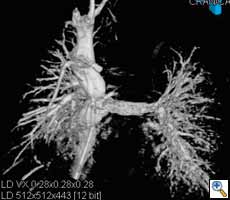

Figure

Figure 1. Hypoplastic left heart syndrome: Intraoperative post-Fontan evaluation of the superior and inferior venae cavae and the stented pulmonary arteries.Courtesy of Prof. Berger, Dr. Ewert Deutsches Herzzentrum, Berlin, Germany

Although surgery remains the treatment of choice for many congenital cardiac malformations, interventional cardiology approaches are increasingly being used in simple and even complex lesions. The percutaneous approach can be challenging due to low patient weight or poor vascular access, induced rhythm disturbances and hemodynamic compromise (2). Difficult and complex anatomy as in double-outlet right ventricle or transposition of the great arteries, or acute turns or kinks in the pulmonary arteries of tetralogy of Fallot patients can make percutaneous procedures challenging if not impossible (19). On the other hand, surgery also has its limitation. Examples are operative closure of multiple apical muscular ventricular septal defects, adequate and lasting relief of peripheral pulmonic stenosis, or management of a previously implanted stenotic stent. Combining interventions and surgery into a single therapeutic procedure leads to reduction of complexity, cardiopulmonary bypass time, risk, and improved outcomes. The hybrid approach to hypoplastic left heart syndrome serves as a role model of the concept (Figure 1) (1, 10).